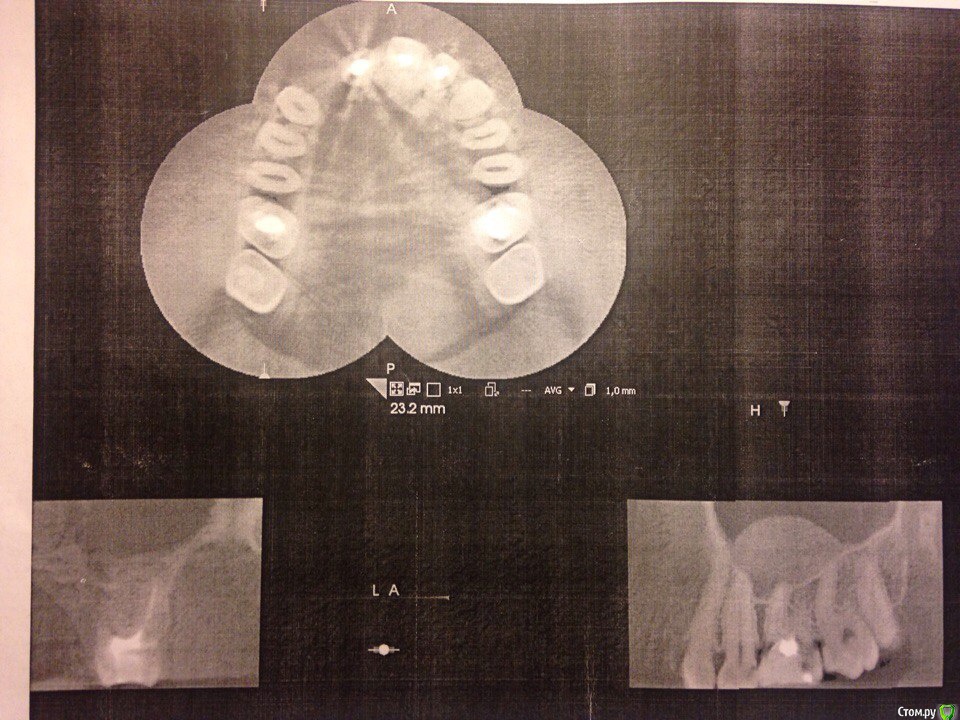

Через 2 месяца решил сделать МРТ носовых пазух и обнаружил, что киста с момента когда я делал МРТ головного мозга выросла. 2,1 на 1,6 см и она связана с корнем 6 зуба верхней челюсти с правой стороны.post-51349-0-57816600-1492620580_thumb.jpg post-51349-0-75262500-1492620585_thumb.jpg post-51349-0-12200600-1492620627_thumb.jpg

В день когда я записался к хирургу, который мне устанавливал имплант, протез выпал совсем. Голова стала болеть немного меньше, но все равно болела. По настоянию врача сделал прицельный рентген где установлен сам имплант и КТ всей челюсти для определения кисты.post-51349-0-78543900-1492620486_thumb.jpg post-51349-0-84336600-1492620557_thumb.jpg Я все сделал и врач установил, что имплант стоит прочно и следует просто заново поставить протез, но лучше по отдельности(не общий для 2 зубов). На КТ кисту он тоже нашёл и направил к челюстному-лицевому хирургу. Поставил мне временный штифт(не знаю как назвать), и на следующий день голова опять начала болеть как прежде.